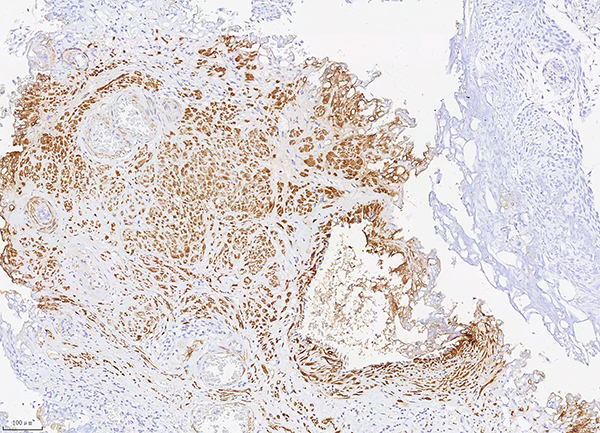

7.AMACR p504s是一種α甲?;o酶A消旋酶,定位于線粒體和過氧化物酶體。在前列腺腺癌和前列腺高級別上皮內(nèi)瘤變中陽性表達(dá),正常前列腺中極少為陽性表達(dá),但在部分前列腺結(jié)節(jié)性增生、非典型腺瘤樣增生也可表達(dá),因此,常與PSA、34βE12、p63等抗體聯(lián)合使用,用于前列腺癌的研究。同時,該抗體也表達(dá)于結(jié)直腸癌、胃癌、卵巢癌、乳腺癌、肺癌等多種腫瘤。

陽性部位:細(xì)胞質(zhì)

樣本類型:腎嗜酸細(xì)胞癌